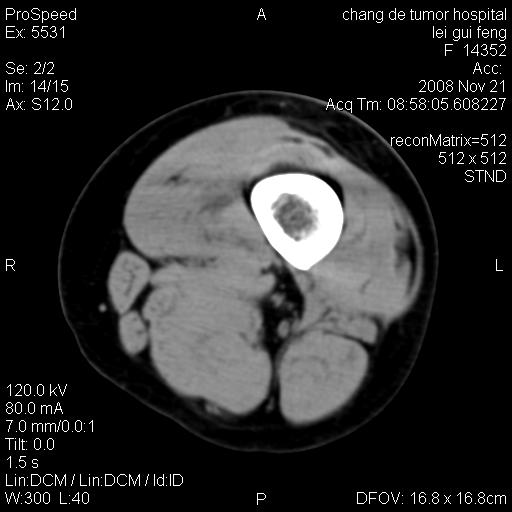

标题: CT16807:女 41 无不适 [打印本页]

标题: CT16807:女 41 无不适

考虑皮样囊肿可能性大

血管瘤可能

血管瘤

血管瘤可能性大!

黏液瘤或表皮杨囊肿

不排除横纹肌肉瘤可能。

血管瘤可能性大或畸胎瘤

考虑脂肪肉瘤

考虑血管瘤可能性大;不排除肉瘤可能。建议行活检。

脂肪肉瘤?

双是软组织肿瘤,病灶内多发钙化,另可见多量脂肪密度影,考虑畸胎瘤,血管瘤,不除外其他